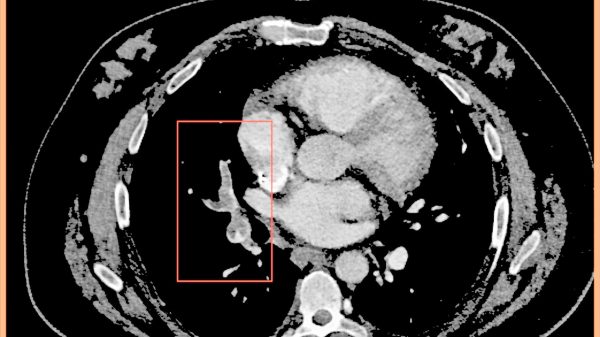

Grafik: Autorenteam